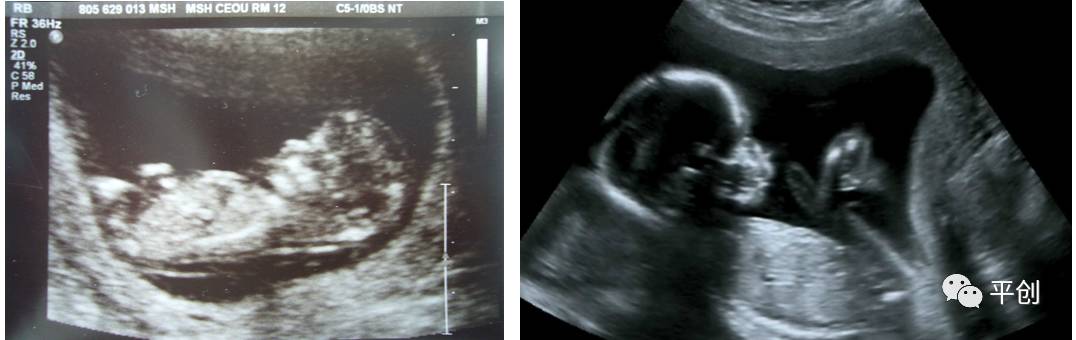

更準(zhǔn)確的醫(yī)學(xué)診斷,來自B超檢查結(jié)果的輔助,準(zhǔn)確的B超檢查結(jié)果,來自B超醫(yī)生看到的B超圖像,清晰的B超成像,來自好的耦合劑。所以說,好的耦合劑對(duì)B超的成像很重要。

而影響B(tài)超檢查成像的因素有兩點(diǎn),一是來自好的探頭,二是來自優(yōu)質(zhì)的耦合劑。如果這兩個(gè)產(chǎn)品其中有一個(gè)質(zhì)量不過關(guān),即對(duì)B超成像有一定程度的影響,可能會(huì)有成像不清楚,醫(yī)生無法準(zhǔn)確判斷所檢查器官的實(shí)際病變,嚴(yán)重的有可能度至醫(yī)生誤診的后果。

普通的卡波姆,其透聲力沒達(dá)到超聲波傳導(dǎo)的系數(shù),無法有效地傳達(dá)聲波,同時(shí)沒有良好的偶合功能,這種情況下,就無法形成清晰的圖像 。

另外,有的廠家的耦合劑濃度太高,或是太稀,涂在檢查部位上,馬上就有一部分水流出,讓患者感到很不舒服,而過稀的耦合劑會(huì)減低其偶合性,過濃的耦合劑難以展開涂抺,或涂抺不均勻,影響探頭在檢查部位的滑動(dòng),這兩種情況都會(huì)減低B超中的耦合性,影響B(tài)超成像的清晰度,從而影響醫(yī)生看到的結(jié)果而給出錯(cuò)誤的判斷,甚至間接的引發(fā)了醫(yī)療事故,嚴(yán)重地影響了醫(yī)院的專業(yè)度和信服力。這些都是醫(yī)生和醫(yī)院及患者都不希望發(fā)生的。

所生產(chǎn)出來的耦合劑無雜質(zhì)、透明度高、不易干,不化水,易偶合、易擦凈,透聲性超過國(guó)家標(biāo)準(zhǔn)的50%(數(shù)據(jù)通過國(guó)家指定的第三方檢測(cè)機(jī)構(gòu)檢測(cè)結(jié)果所得),完全地解決了成像不清晰的難題。

安創(chuàng)安必潔耦合劑已經(jīng)在廣東省人民醫(yī)院、南方醫(yī)院、中山大學(xué)附屬第一醫(yī)院等全國(guó)各三甲醫(yī)院使用,并得到了各醫(yī)院的一致認(rèn)可,解決了其它品牌耦合劑的偶合性差、透聲功能低,成像不清晰的問題,減少了B超結(jié)果誤診的機(jī)率,同時(shí)也解決了短期內(nèi)要多次尋找耦合劑品牌的煩惱,所以得到了各合作醫(yī)院的聯(lián)合推薦使用:“好的耦合劑,選用安創(chuàng)安必潔消毒耦合劑。